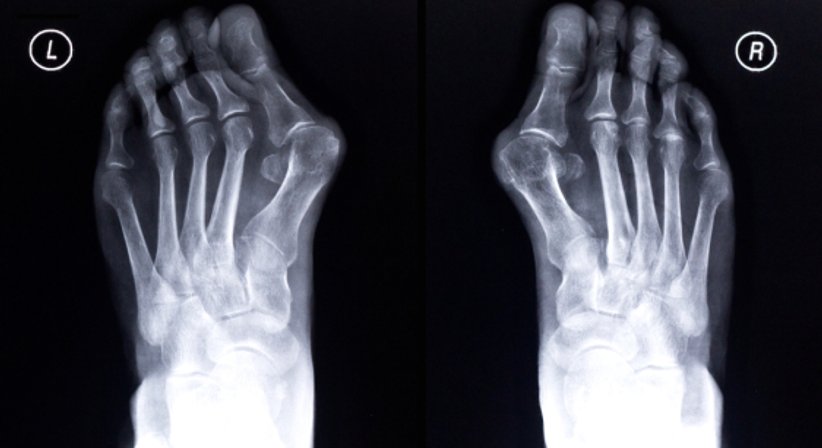

Beim Hallux valgus handelt es sich um eine Deformität der Großzehe und um eine der häufigsten Zehenfehlstellungen beim Menschen.

Für viele Betroffene stellt die Fehlstellung anfangs vor allem ein kosmetisches Problem dar, allerdings ist der Hallux valgus vor allem ein Hinweis auf eine gestörte Biomechanik und eine Funktionsstörung des Fußes, welche möglichst frühzeitig behandelt werden sollte, um Begleiterkrankungen des Fußes und weitere Fehlstellungen zu vermeiden - denn dadurch, dass die Großzehe zum Außenrand des Fußes hin abweicht, werden die kleineren Zehen nach und nach von ihrer natürlichen Position vertrieben.

Weiters kommt es durch die Fehlstellung zu einer Überlastung des Großzehengrundgelenks, was vorzeitigen Gelenkverschleiß fördern kann. Verdrängte Kleinzehen (Krallenzehen, Hammerzehen) können weitere Fußdeformitäten zufolge haben, weiters kann es zu Schmerzen im Bereich des Mittelfußes kommen, da die Großzehe nicht mehr voll eingesetzt wird, was zu einer Überlastung der kleineren Zehen führt.